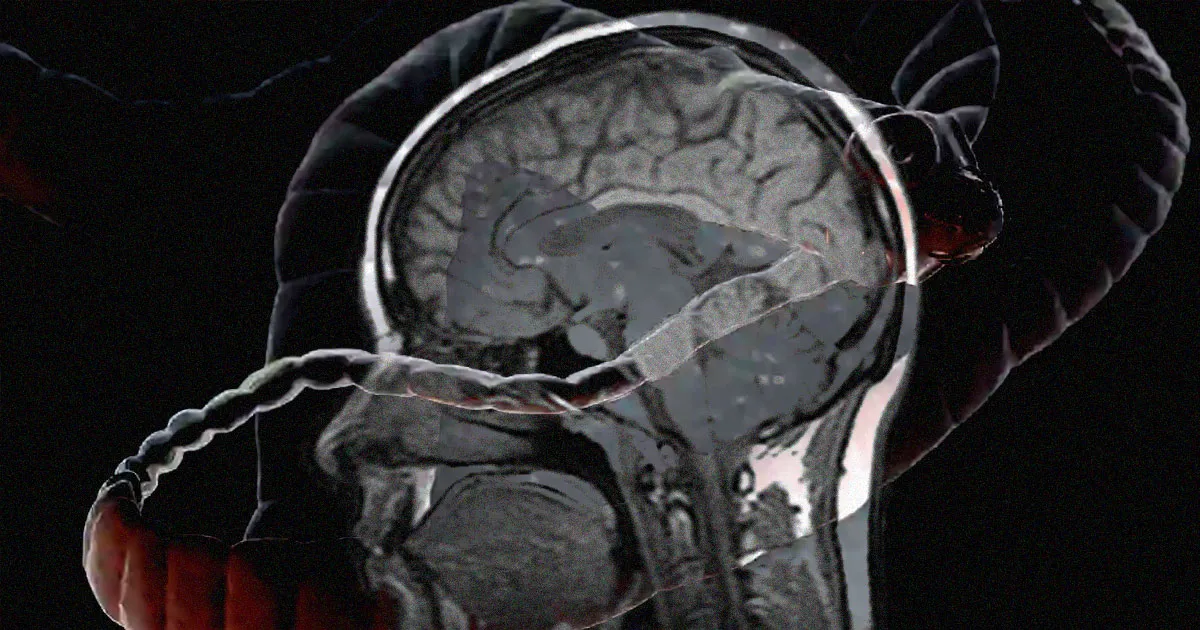

Un scanner cérébral a révélé des lésions calcifiées sur son cerveau, menant les médecins à diagnostiquer une condition connue sous le nom de neurocysticercose. Cette infection parasitaire est causée par des larves de vers solitaires qui s’étaient introduites dans son cerveau des années auparavant.

Les médecins ont fait paraître leurs résultats dans une étude de cas publiée dans The New England Journal of Medicine. Selon eux, l’homme aurait contracté le ver lors de son séjour dans une région rurale du Guatemala, où ce parasite est courant.